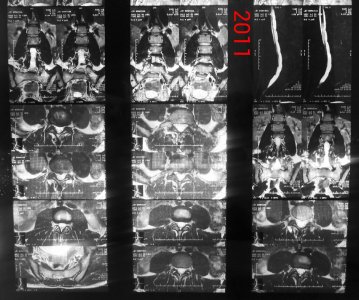

Здравствуйте! Я парень, мне 21 год, рост 190, вес 90, у меня поясничные грыжи l1-l2 1,8 мм, l2-l3 3,5 мм, l5-s1 4,4 мм, беспокоит уже 1,5 года слабость в ногах сначала была боль в левой ноге затем исчезла, и появилась постепенно слабость с внешней стороны квадрицепса до большого пальца ноги, и справа от колена по внешней стороне до большого пальца вниз, больше интересует непостоянность этих симптомов, то есть они могут вообще исчезать на один день и появляться на другой, могут появиться просто когда лежал телевизор смотрел и при этом спина вообще не болит, и в ногах боли тоже нет, невролог проводивший осмотр направлял на вич, гепатит, сифилис все чисто. Если начинаю пить прозерин по 2 таблетки в день все как рукой снимает. Ниже приведены все снимки и заключения имеющиеся на руках.Что это может быть, почему слабость может так быстро исчезать и появляться снова, грыжи то на месте может это что то другое? И еще хотелось бы узнать ваше мнение по поводу записи в заключении 2013 года (Арахноидальная киста в мягких тканях на уровне межостистых отростков L5-S1 7x8-8x2 мм) она не может сдавливать нервы?